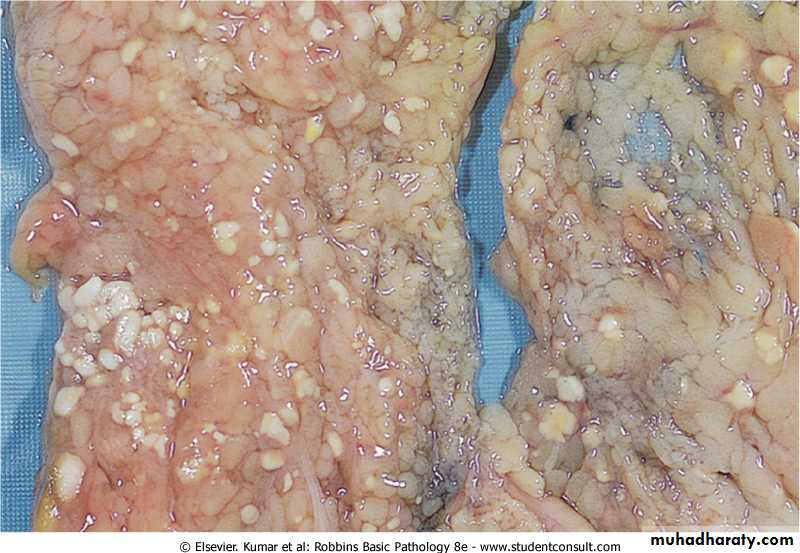

Fat necrosis typically seen in acute pancreatitis and results from release of activated pancreatic lipases into the substance of the pancreas and the peritoneal cavity. Pancreatic enzymes that have leaked out of acinar cells liquefy the membranes of fat cells releasing fatty acids that combined with calcium to produce grossly visible chalky white areas (fat saponification).this typical appearance enables the surgeon to identify the lesions. Microscopically the foci of necrosis contain shadowy outlines of necrotic fat cells with bluish calcium deposits surrounded by an inflammatory reaction. Another example of fat necrosis is seen in female breasts; at least some of these cases are preceded by a history of trauma (traumatic fat necrosis)

Fat necrosis in acute pancreatitis. The areas of white chalky deposits represent foci of fat necrosis with calcium soap formation (saponification) at sites of lipid breakdown in the mesentery.